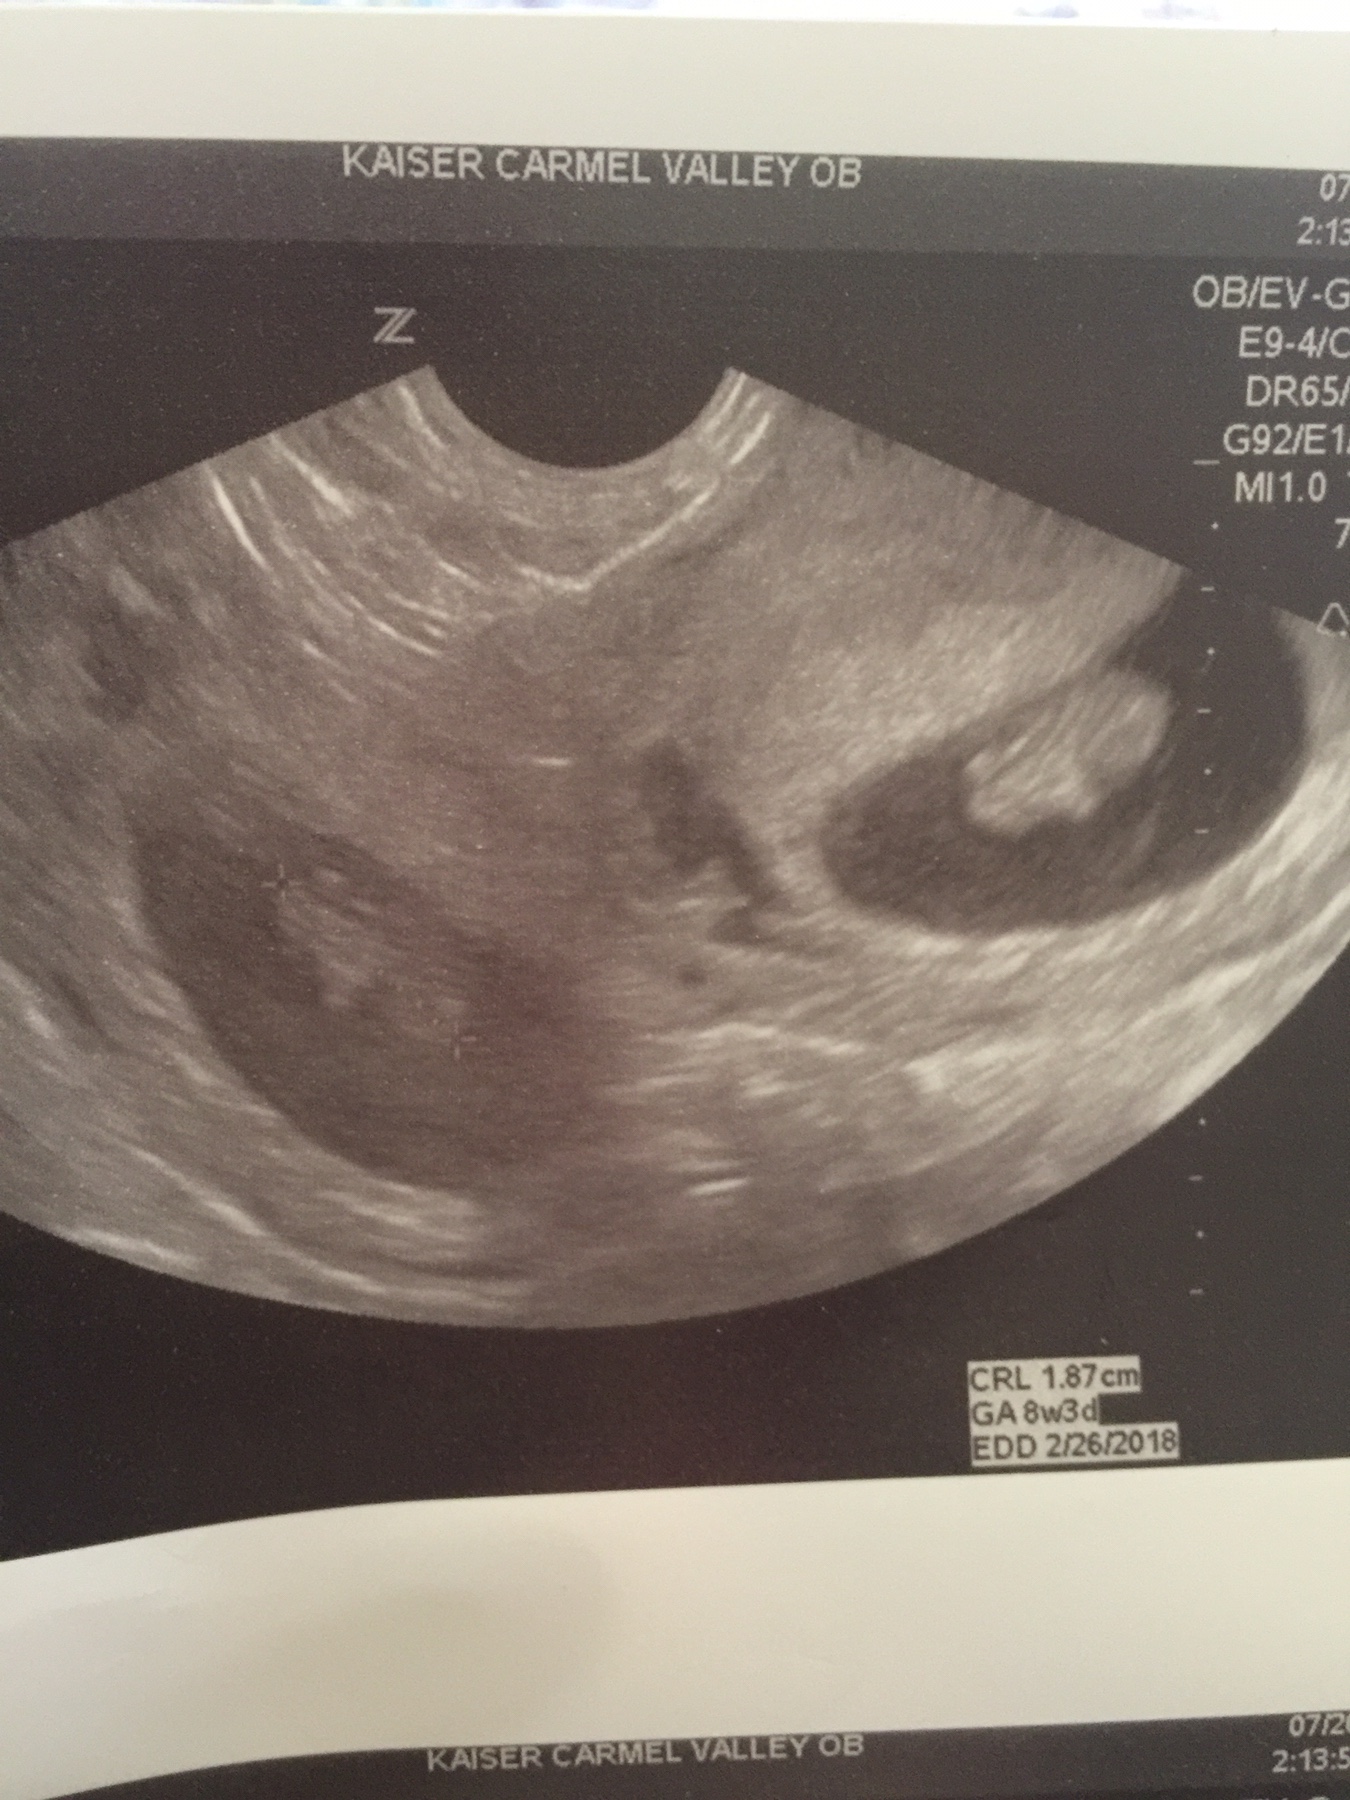

Ramzi theory any one for my twins . This is my 8 weeks transvaginal ultrasound . This is my 3rd pregnancy I have 2 girls.Attachment 37237

Ramzi theory has been debunked. It's also impossible to tell what angle the tech took the pics at. Cute babies though! Congrats on the twins!!